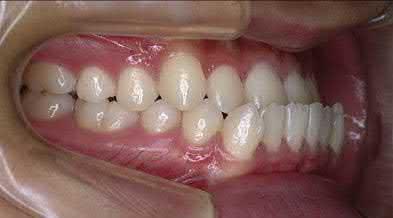

Cover Images: (top left) Image of human teeth courtesy of Joorok Park, (bottom left) line drawing of human gum courtesy of KJ Lee, (right) Scanned image of human skeleton courtesy of Dr. Tung Nguyen